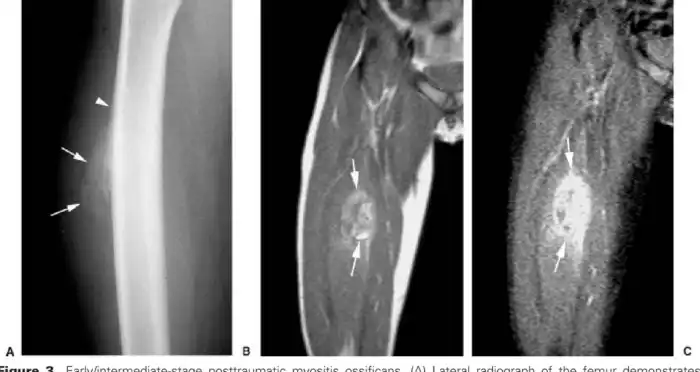

В первую очередь Юлиус пытается сравнить болезнь с Myositis ossificans circumscripta - схожим феноменом доброкачественных неопухолевых костных образований в мышцах и мягких тканях. Сегодня считается, что MОС, или оссифицирующий приобретенный миозит, имеет травматическую причину и более точное современное его название - myositis ossificans traumatica. Хотя механизм заболевания является загадкой, 80% появления «окаменелостей» в мышцах, преимущественно бедер и рук, являются последствием именно физической травмы. В отличии от фибродисплазии, эти камни единичны и не разрастаются так обширно. Хотя в некоторых случая межреберные пространства и грудные мышцы замещаются костной тканью в достаточно больших объемах. Возможно, вам это покажется отсылкой на суперспособности, когда после сильной травмы вы становитесь сильней, а ваши кости крепче. Что ваши ребра срастаются вместе, утолщаются за счет окостенения мышечной ткани и создают вам бронежилет, делающий вас неуязвимыми. Ну что же... это не так. Вообще, фраза о том, что сломанные кости становятся крепче, может звучать только от тех, кто их не ломал, а потом не сидел, обняв кота в свои 50 лет в дождливый вечер у окна. Реальность очень и очень далека от таких мифов, заключающихся в инвалидности, ограничении подвижности, проблемам с позвоночником и болями, в сравнении с которыми ваша межреберная невралгия даже рядом не стоит.

Костное образование в мышце на ноге: